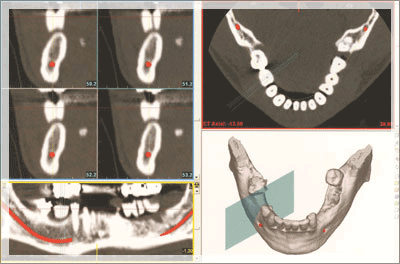

画像解析

CT装置ガリレオスによりお口の状態を撮影します。顎骨形態、骨質を3次元で解析し、数値と画像で精確な情報を把握します。セレックシステムのプライムスキャンにより歯列データをスキャニングします。